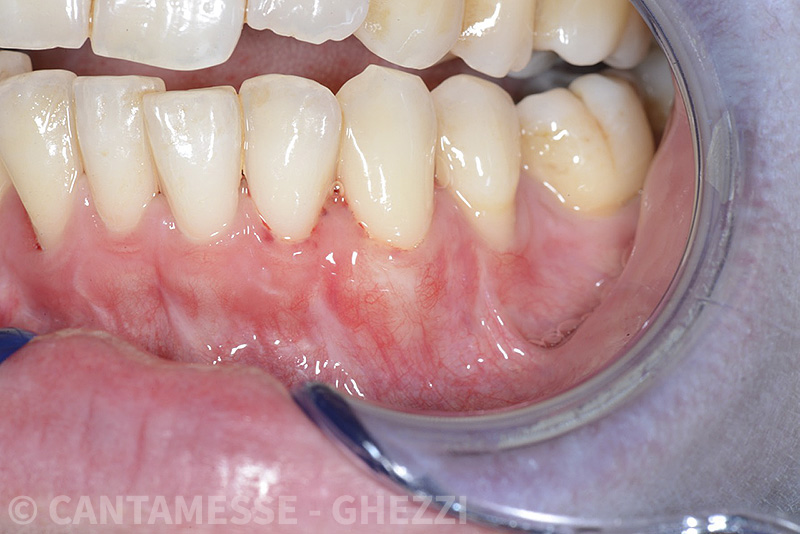

Vengono utilizzati 2 tipi di provvisori: il primo, cementato ai denti vicini, viene utilizzato dal momento dell’estrazione del dente fino ad impianto osteointegrato (circa 6 mesi); il secondo, avvitato direttamente all’impianto, ha una funzione di prova estetica ma soprattutto di guida per la maturazione dei tessuti gengivali peri-implantari portandoli verso la maturazione completa prima di posizionare la corona finale in disilicato di litio.